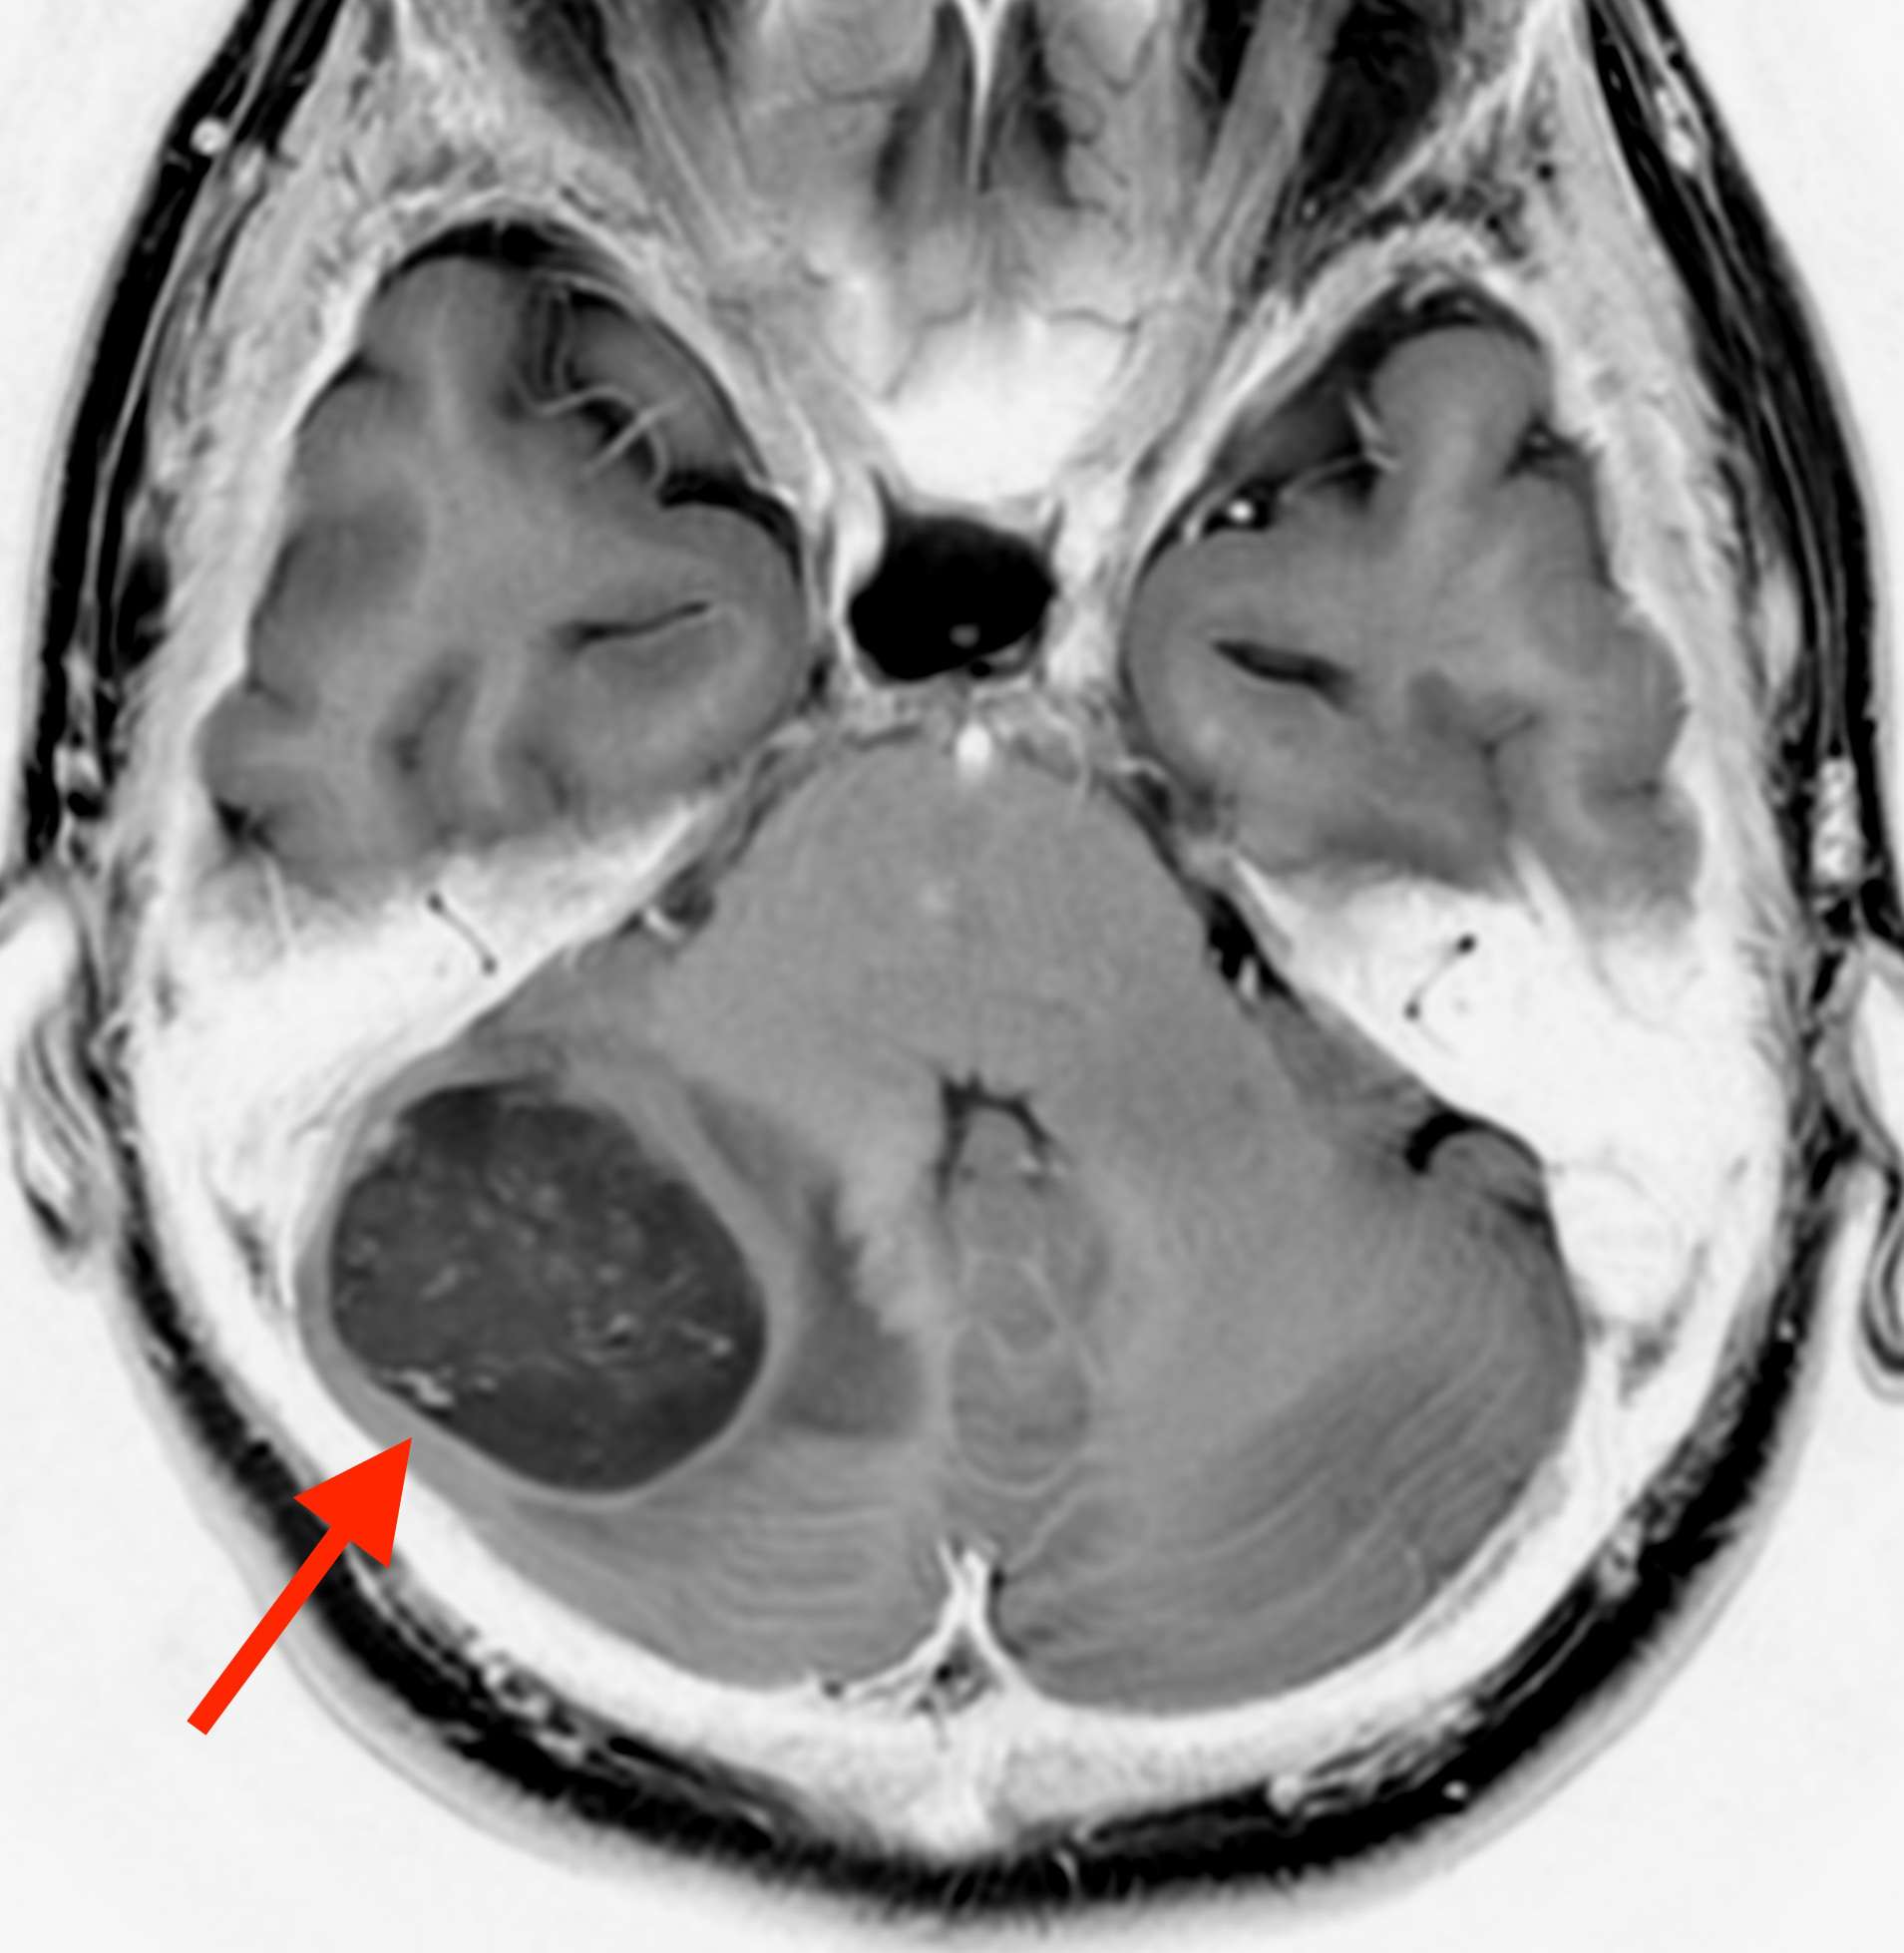

MRI検査をしたところ、

右の小脳に直径3.6mm位の脳腫瘍が見つかりました。小脳は体のバランスをコントロールしている場所です。つまり、ここが侵されるとめまいやふらつきを感じるようになります。

頭痛とめまいや吐き気がある場合、こうした脳の病気である場合もあります。

したがって、この方は精密検査や手術が必要と考え、総合病院へ紹介させていただきました。